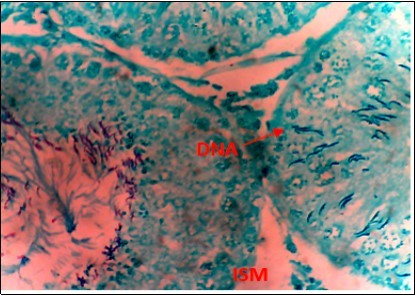

Figure 7.(DC+1000mg/kg.bw of AP) X400 – Section of testis showing scanty DNA deeply stained with magenta color. DNA strands has reduced clusters

From findings in this study, irregular and distorted arrangements of DNA in all diabetic groups (Groups B, C, D, E and F) when compared with the normal control group, may have been due to displacement of sertoli cell within the germinal epithelium of seminiferous tubules. Strands of DNA were also seen arrange in clusters in diabetic groups, showing altered and defective structure which might have resulted from base free side deletion, frame shift, cross-linking and chromosomal rearrangement. The intensity of magenta colour development in Feulgen reaction for DNA demonstration was proportional to DNA concentration. There was reduced colour intensity in all diabetic groups (Groups B, C, D, E and F) when compared with the normal control. This is in line with report from Aitken and Krausz (2001). However the degree of distortion and cross-linking of DNA strand in the group of diabetic animal models placed on high dose (1000mg/kg.bw) of A. polytricha which may be a sign of amelioration. Groups C, D and F placed on 250mg/kg.bw A. polytricha, 500mg/kg.bw A. polytricha and standard anti-diabetic drug (metformin) respectively did not show remarkable differences in terms of DNA arrangements when compared with the diabetic control group. Groups D (500mg/kg.bw A. polytricha) and group E (1000mg/kg.bw) showed visible improvement in magenta colour intensity when compared with the diabetic control group.

The marginal reversal of DNA damage following 21 days of A. polytricha administration, as observed in this study may be linked to its polysaccharides constituent found to exhibit antimutagenic effect against in-vivo DNA damaging activities of indirectly acting alkylating agent. A. polytricha may have improved antioxidant status of experimental animals and was capable of ameliorating DNA damage which may be attributed to its potentials to regulate concentration of carboxymethyllysine (CML) and advanced glycation end (AGE) which are important triggers of oxidative stress in the reproductive tract of diabetic animals. AP is known to be a good exogenous source of antioxidant and may have ameliorated further DNA damage.